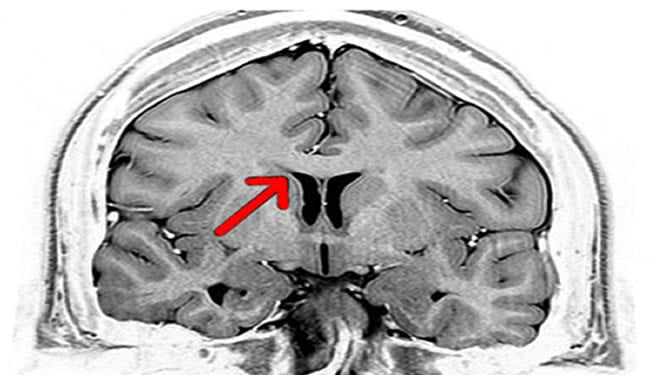

Brain imaging studies of women with breast cancer before and after chemotherapy treatments show grey matter is being affected during the chemotherapy treatments. Brain areas believed to be critical for multi-tasking, memory and other cognitive functions were seen to change during the chemotherapy.